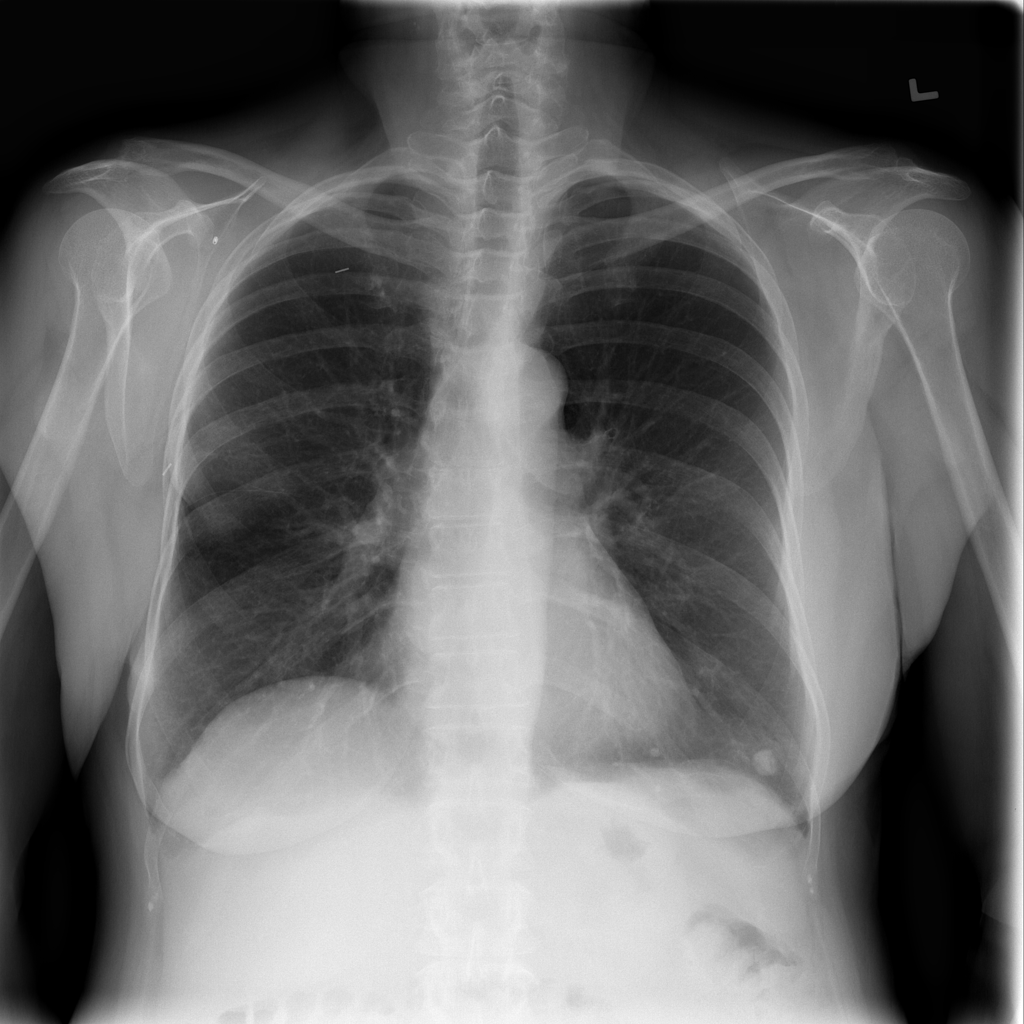

Nodule

A nodule is a small rounded opacity in the lung or chest field. It is a descriptive imaging finding that can be benign or more concerning depending on size, appearance, and context.

Showing up to 90 reference images for Nodule.

PAT-FB8F · IMG-000Nodule

PAT-FB8F · IMG-000

PA